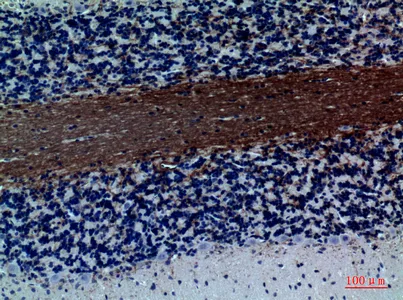

Catenin-β Rabbit Polyclonal Antibody

Cat: APRab08004

Size1:50μl Price1:$118

Size2:100μl Price2:$220

Size3:500μl Price3:$980

Size2:100μl Price2:$220

Size3:500μl Price3:$980